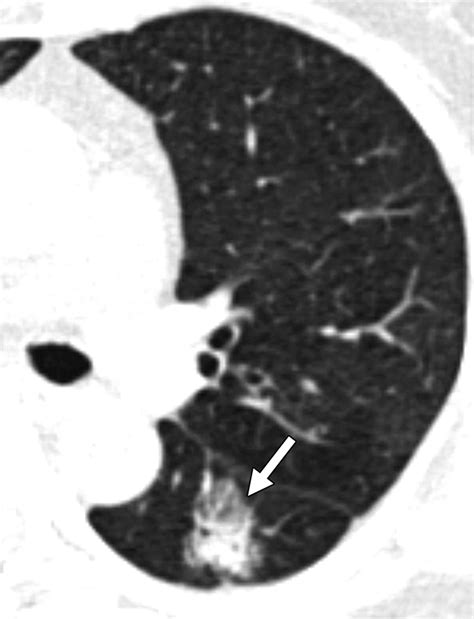

A ground glass nodule (GGN) refers to a hazy, cloudy opacity within the lungs that appears on a CT scan. Unlike solid nodules, which are dense enough to completely obscure the underlying lung tissue, a GGN allows the structures of the lung, such as the airways and blood vessels, to remain visible through the haze. The term derives from the visual similarity to glass that has been treated to appear frosted or translucent.

• Consistency: Whether the nodule is "pure" (completely hazy) or "part-solid" (containing a denser core).

While the majority of these nodules are benign or very slow-growing, there are specific "red flags" that may prompt a more aggressive diagnostic approach. If a ground glass nodule begins to develop a larger solid component, or if it shows a rapid increase in size over a short timeframe, your medical team may transition from surveillance to diagnostic testing. This could involve a PET scan to check for metabolic activity or a biopsy to extract a tissue sample for laboratory analysis.